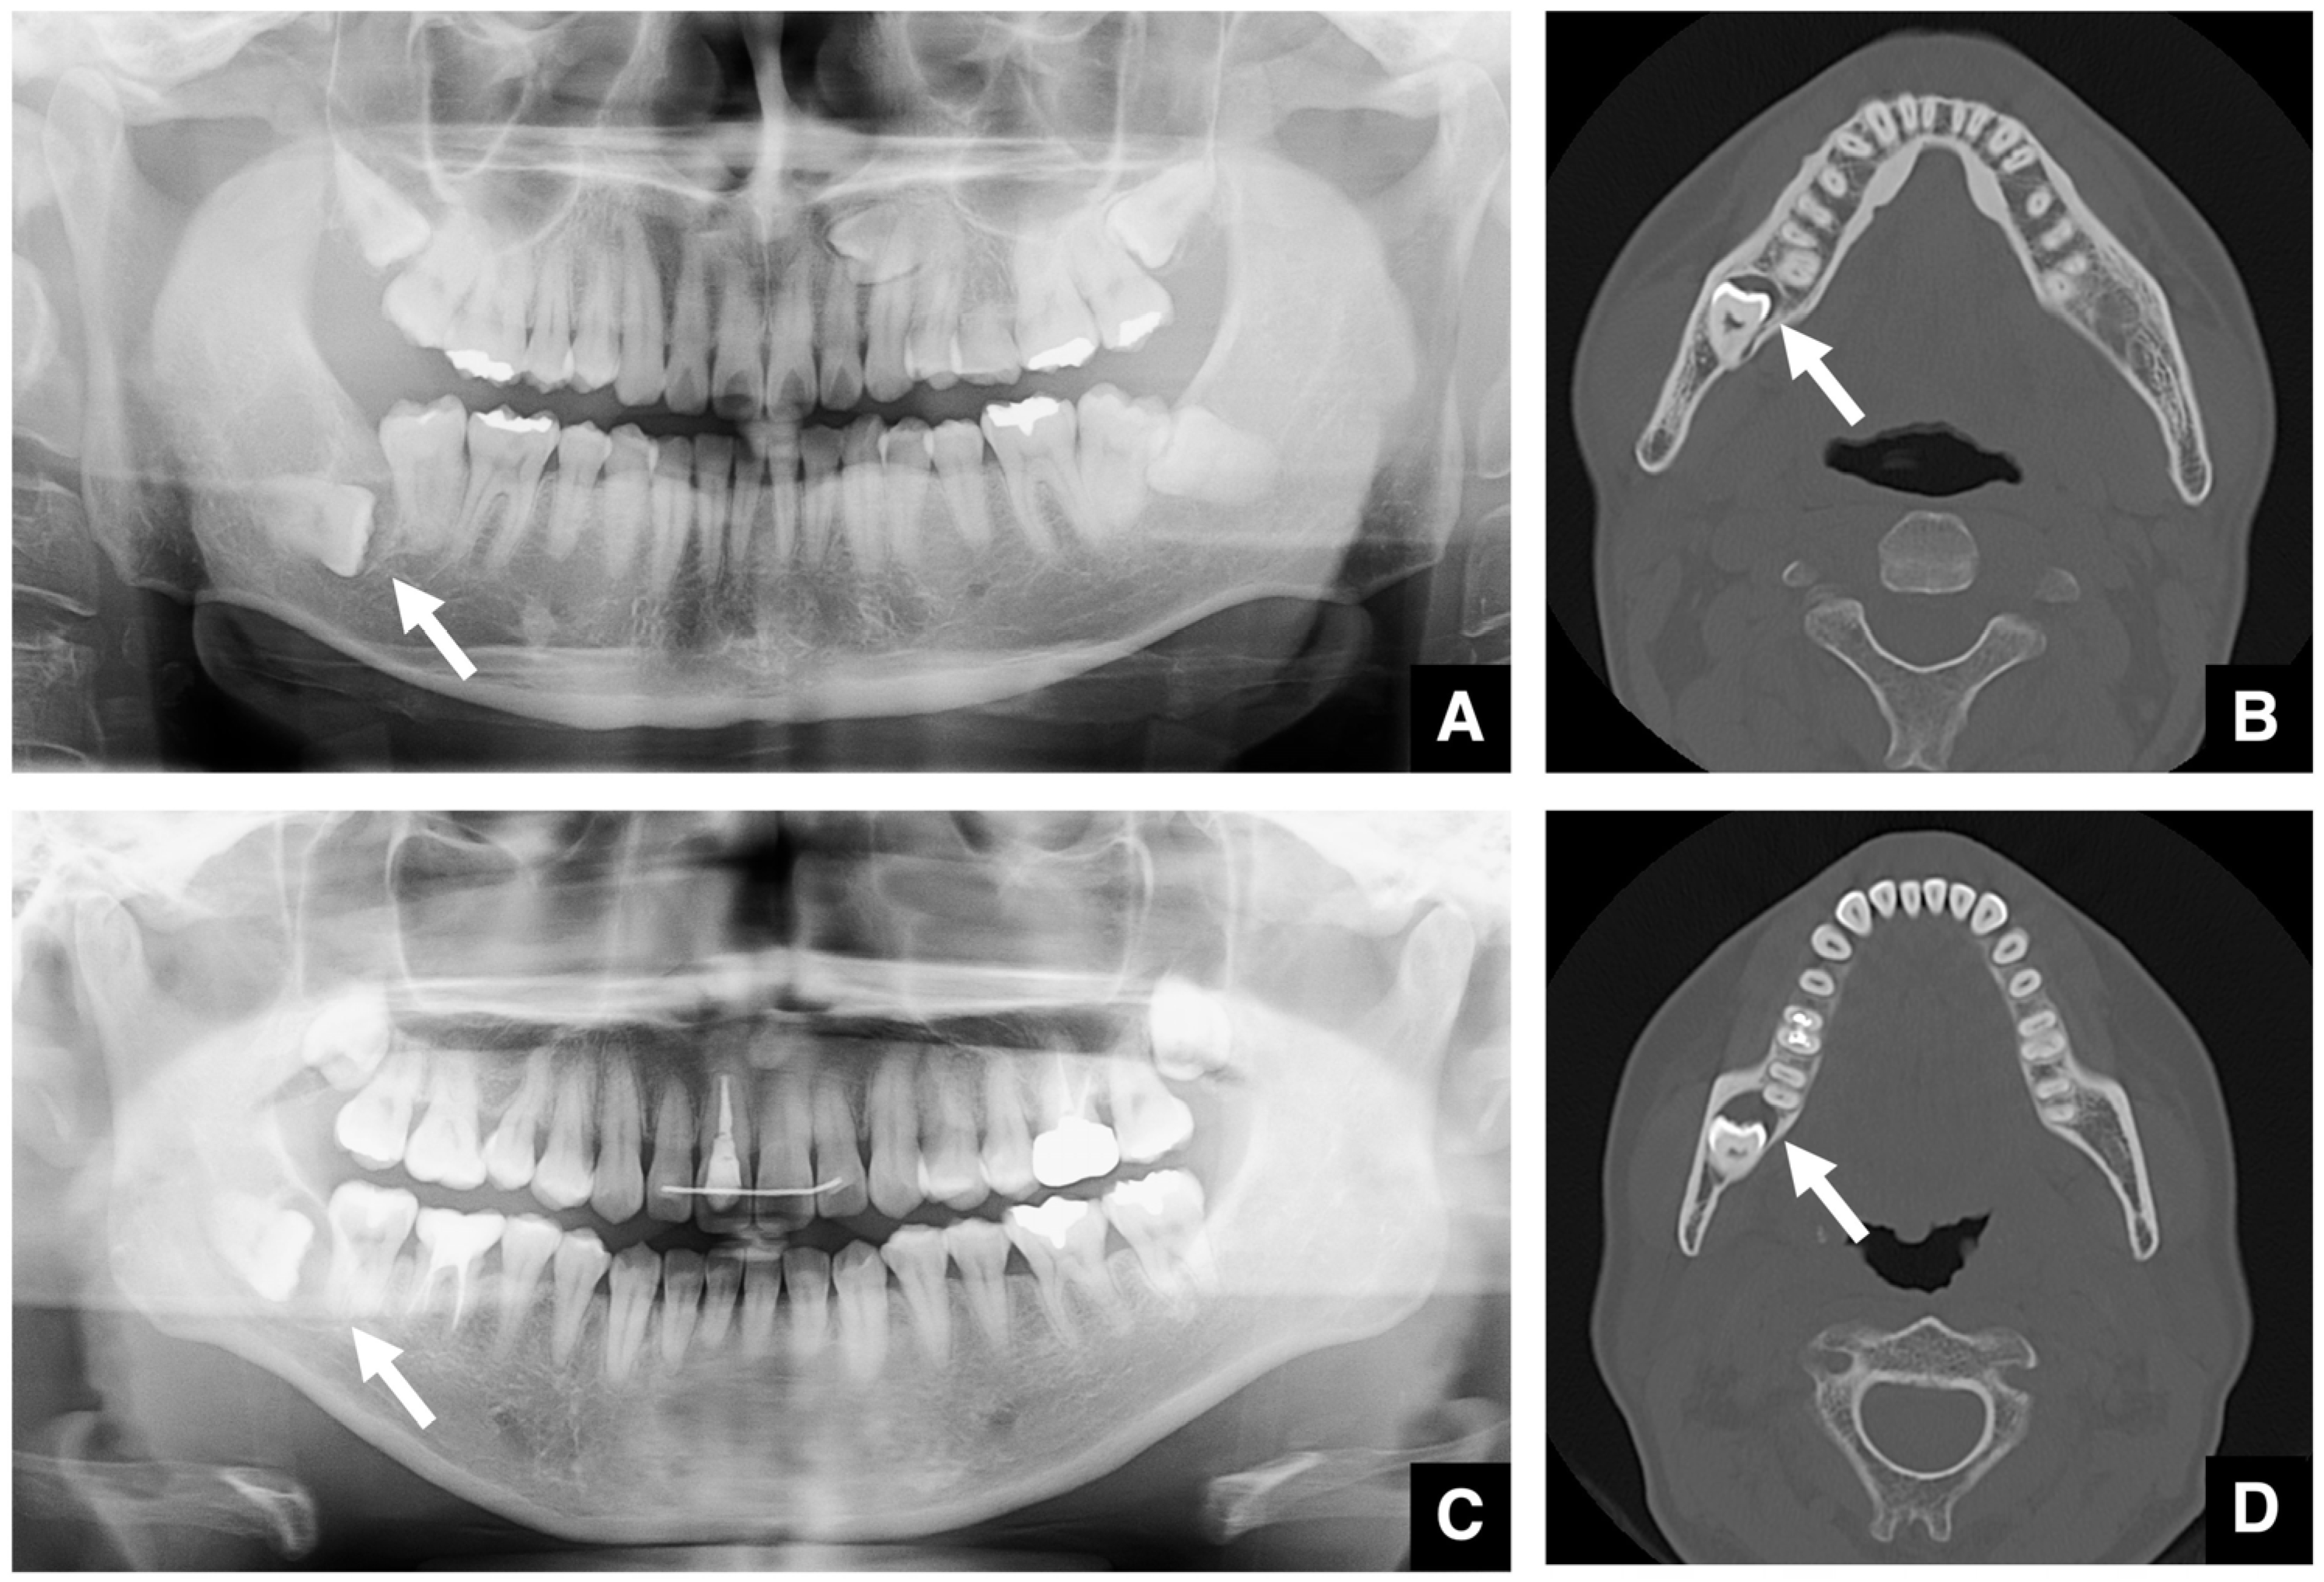

| Setting the osteotomy line 1. Evaluation of the position of the mandibular canal and surrounding bone quality Presence or absence of mandibular canal bifurcation and course of resection site Distance from the buccal wall of the mandibular canal to the buccal cortical bone margin Bone quality around the mandibular canal (CT number) 2. Distance from the mandibular notch to the lingula Whether it is 14 mm or more 3. Morphology of the mandible and variation in cortical bone thickness Cortical bone thickness in the medial osteotomy area and lateral osteotomy area Enhanced safety through improved visibility 1. Medial curvature of the mandibular ramus Mandibular ramus is straight or strong curvature 2. Course of small blood vessels along the bone surface Depression of the buccal-lingual cortical bone from the mandibular fossa to the mandibular ramus region, trabecular bone defect Improved success rates through enhanced postoperative bone integration 1. Degree of interference between bone segments The presence or absence of interference between the proximal and distal bone segments formed during virtual mandibular deformity surgery |